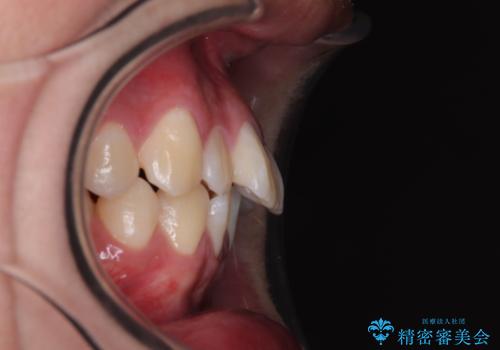

特に前歯のデコボコが顕著であり、上下左右第一小臼歯の4本を抜歯し、ワイヤー装置を使用して咬み合わせ高さを改善しながら、歯列を整えて行くこととしました。

移動が順調に進み、1年半の短期間で治療を終えることができました。

前方に突出した上顎前歯の傾斜も改善されました。